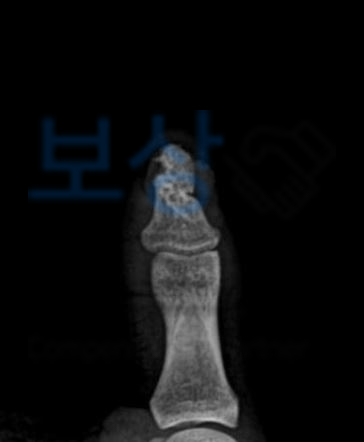

세종시 거주하시는 김@@님은 식품을 생산하기 위한 작업준비 중 금형 몰드에 손가락이 끼이는 재해가 발생하였습니다. 이로인해 김@@님은

좌측 무지 절단손상(골절 포함)

진단을 받으셨고